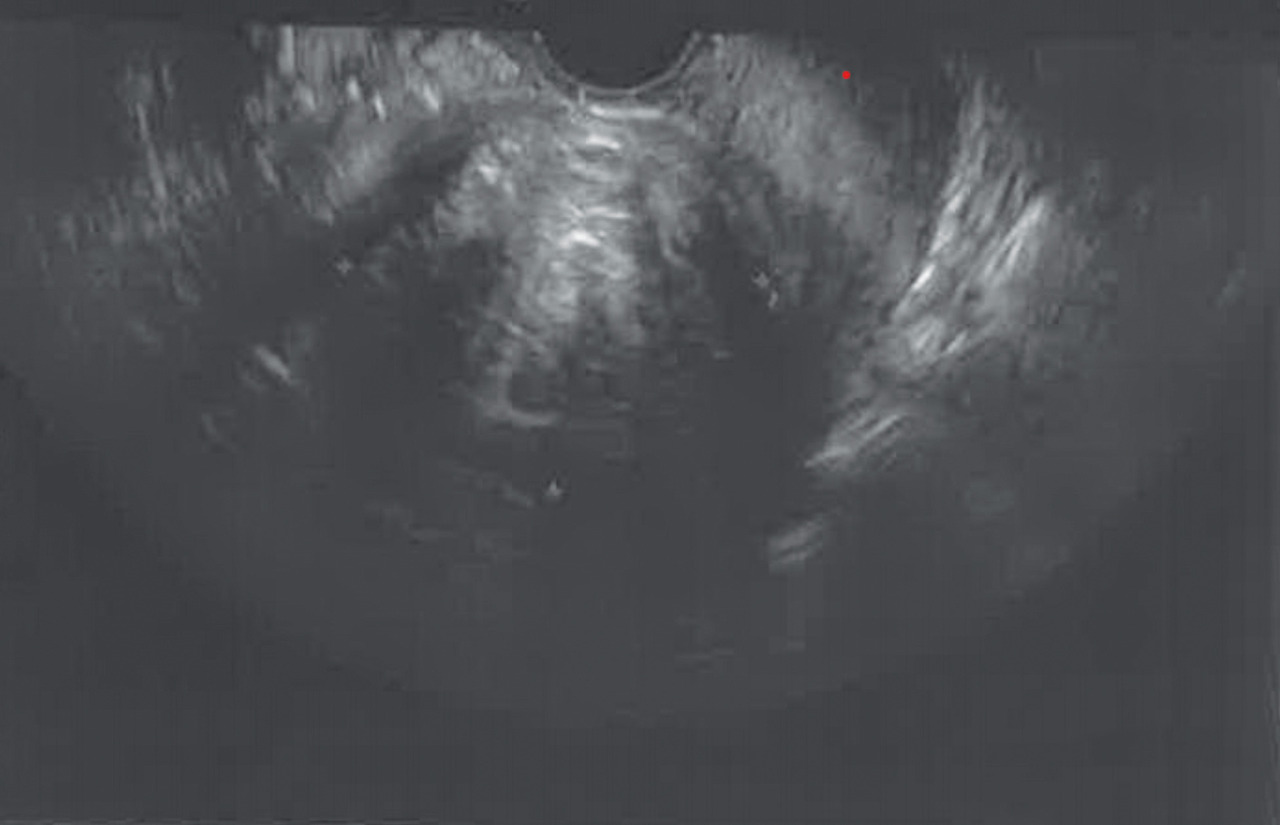

Échographie pelvienne (2D ou 3D)

Elle est toujours indiquée en cas d’hémorragie génitale d’origine haute, réalisée par voie sus-pubienne dans un premier temps, puis par voie endovaginale, vessie vide, dans un deuxième temps.Elle mesure la taille de l’utérus, qui est augmentée en cas d’adénomyose ou de fibrome.

Elle visualise les annexes et s’assure de la normalité de celles-ci.

Enfin, elle vérifie la présence ou non d’un épanchement dans le cul-de-sac de Douglas.